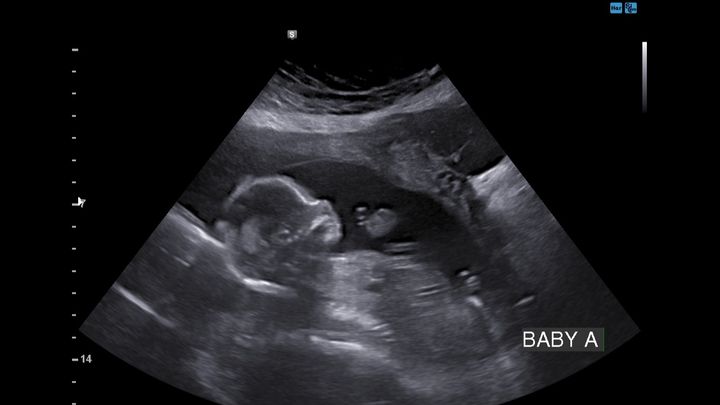

Brittany was recently diagnosed with Sjögren's Syndrome and hospitalized for the past week due to complications with baby A and her heart. Baby A has a complete heart block, with fluid around the heart and abdomen and does not have a good prognosis. Brittany will have to continue infusions, as well as numerous appointments 2+ times a week to monitor baby A's current condition with possible extensive medical travel in the future as things progress.